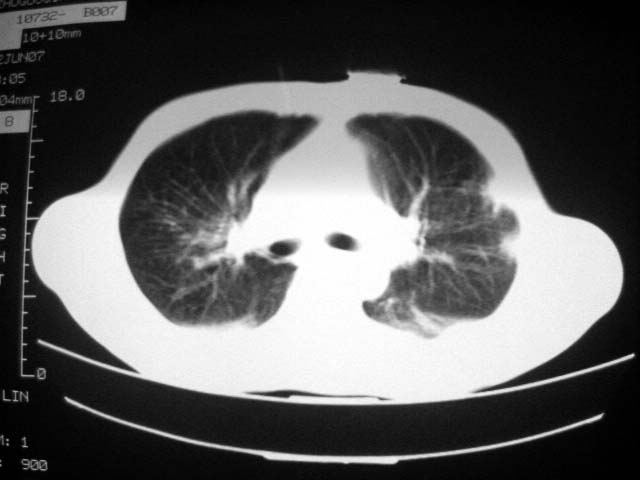

近2个月病灶变化较大,应是感染性病变,首先考虑金黄色葡萄球菌感染。

根据前后片比较应该考虑迁徙性肺脓肿,回帖相差甚远是因为前后片变化太大出乎大家意料之外,这就是影象诊断要结合临床复查对比的必要性,

回顾既往片,病变明显吸收,缩小,未经治疗,不支持肺转移瘤,可能为肺结节病或韦格氏肉芽肿

支持韦格氏肉芽肿